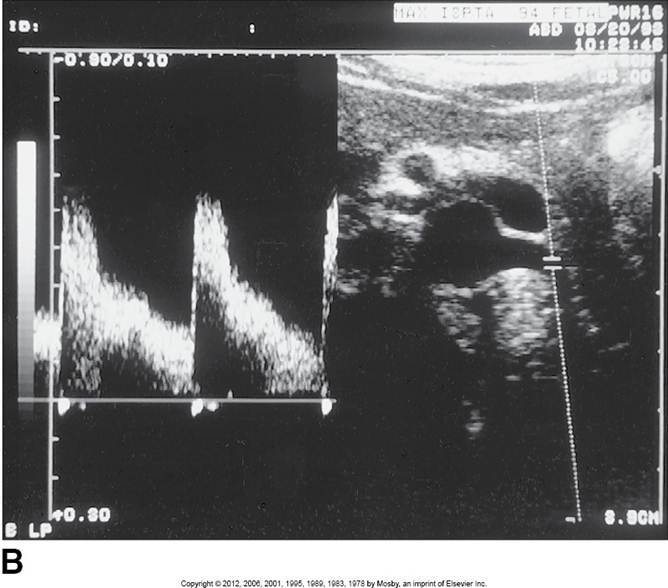

Hepatic Artery